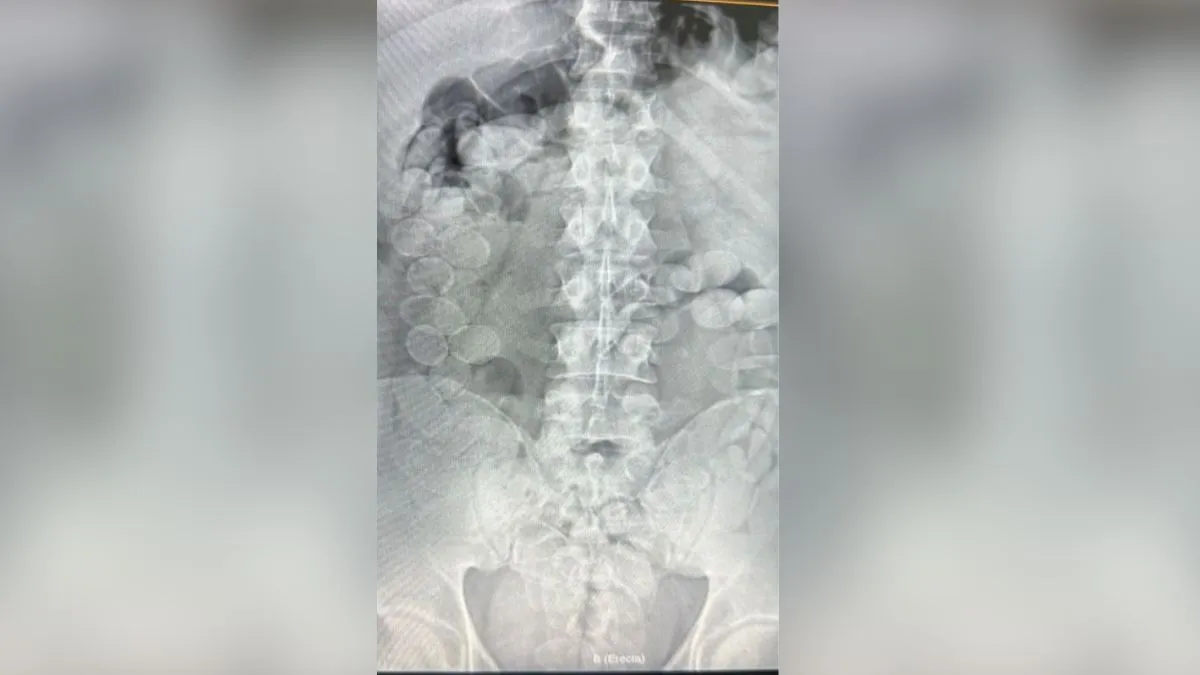

Las dos personas mostraron signos de descompostura, por lo que fueron trasladados a un hospital local. Allí se le realizaron placas radiográficas que confirmaron la sospecha: dentro de sus cuerpos tenían entre 80 y 90 cápsulas de cocaína cada uno.

Los sospechosos iban en un colectivo de pasajeros rumbo a Buenos Aires y manifestaron descompostura, por lo que fueron trasladados a un hospital donde se les realizaron placas que mostraron cápsulas de cocaína en su organismo.

En un operativo sobre la Ruta Nacional 34 a la altura de Ceres, la Gendarmería Nacional Argentina (GNA) detuvo a dos personas con más de 160 cápsulas de cocaína dentro de su organismo. Los detenidos venían en un colectivo de pasajeros desde Jujuy y son de nacionalidad boliviana.

Acto seguido, se realizaron procedimientos de evacuación de los envoltorios bajo estricto control médico, debido a que son procedimientos de riesgo porque la ruptura de una cápsula implicaría graves riesgos para la salud.

Tras remover la droga, se constató que cada uno cargaba con más de un kilo de cocaína.